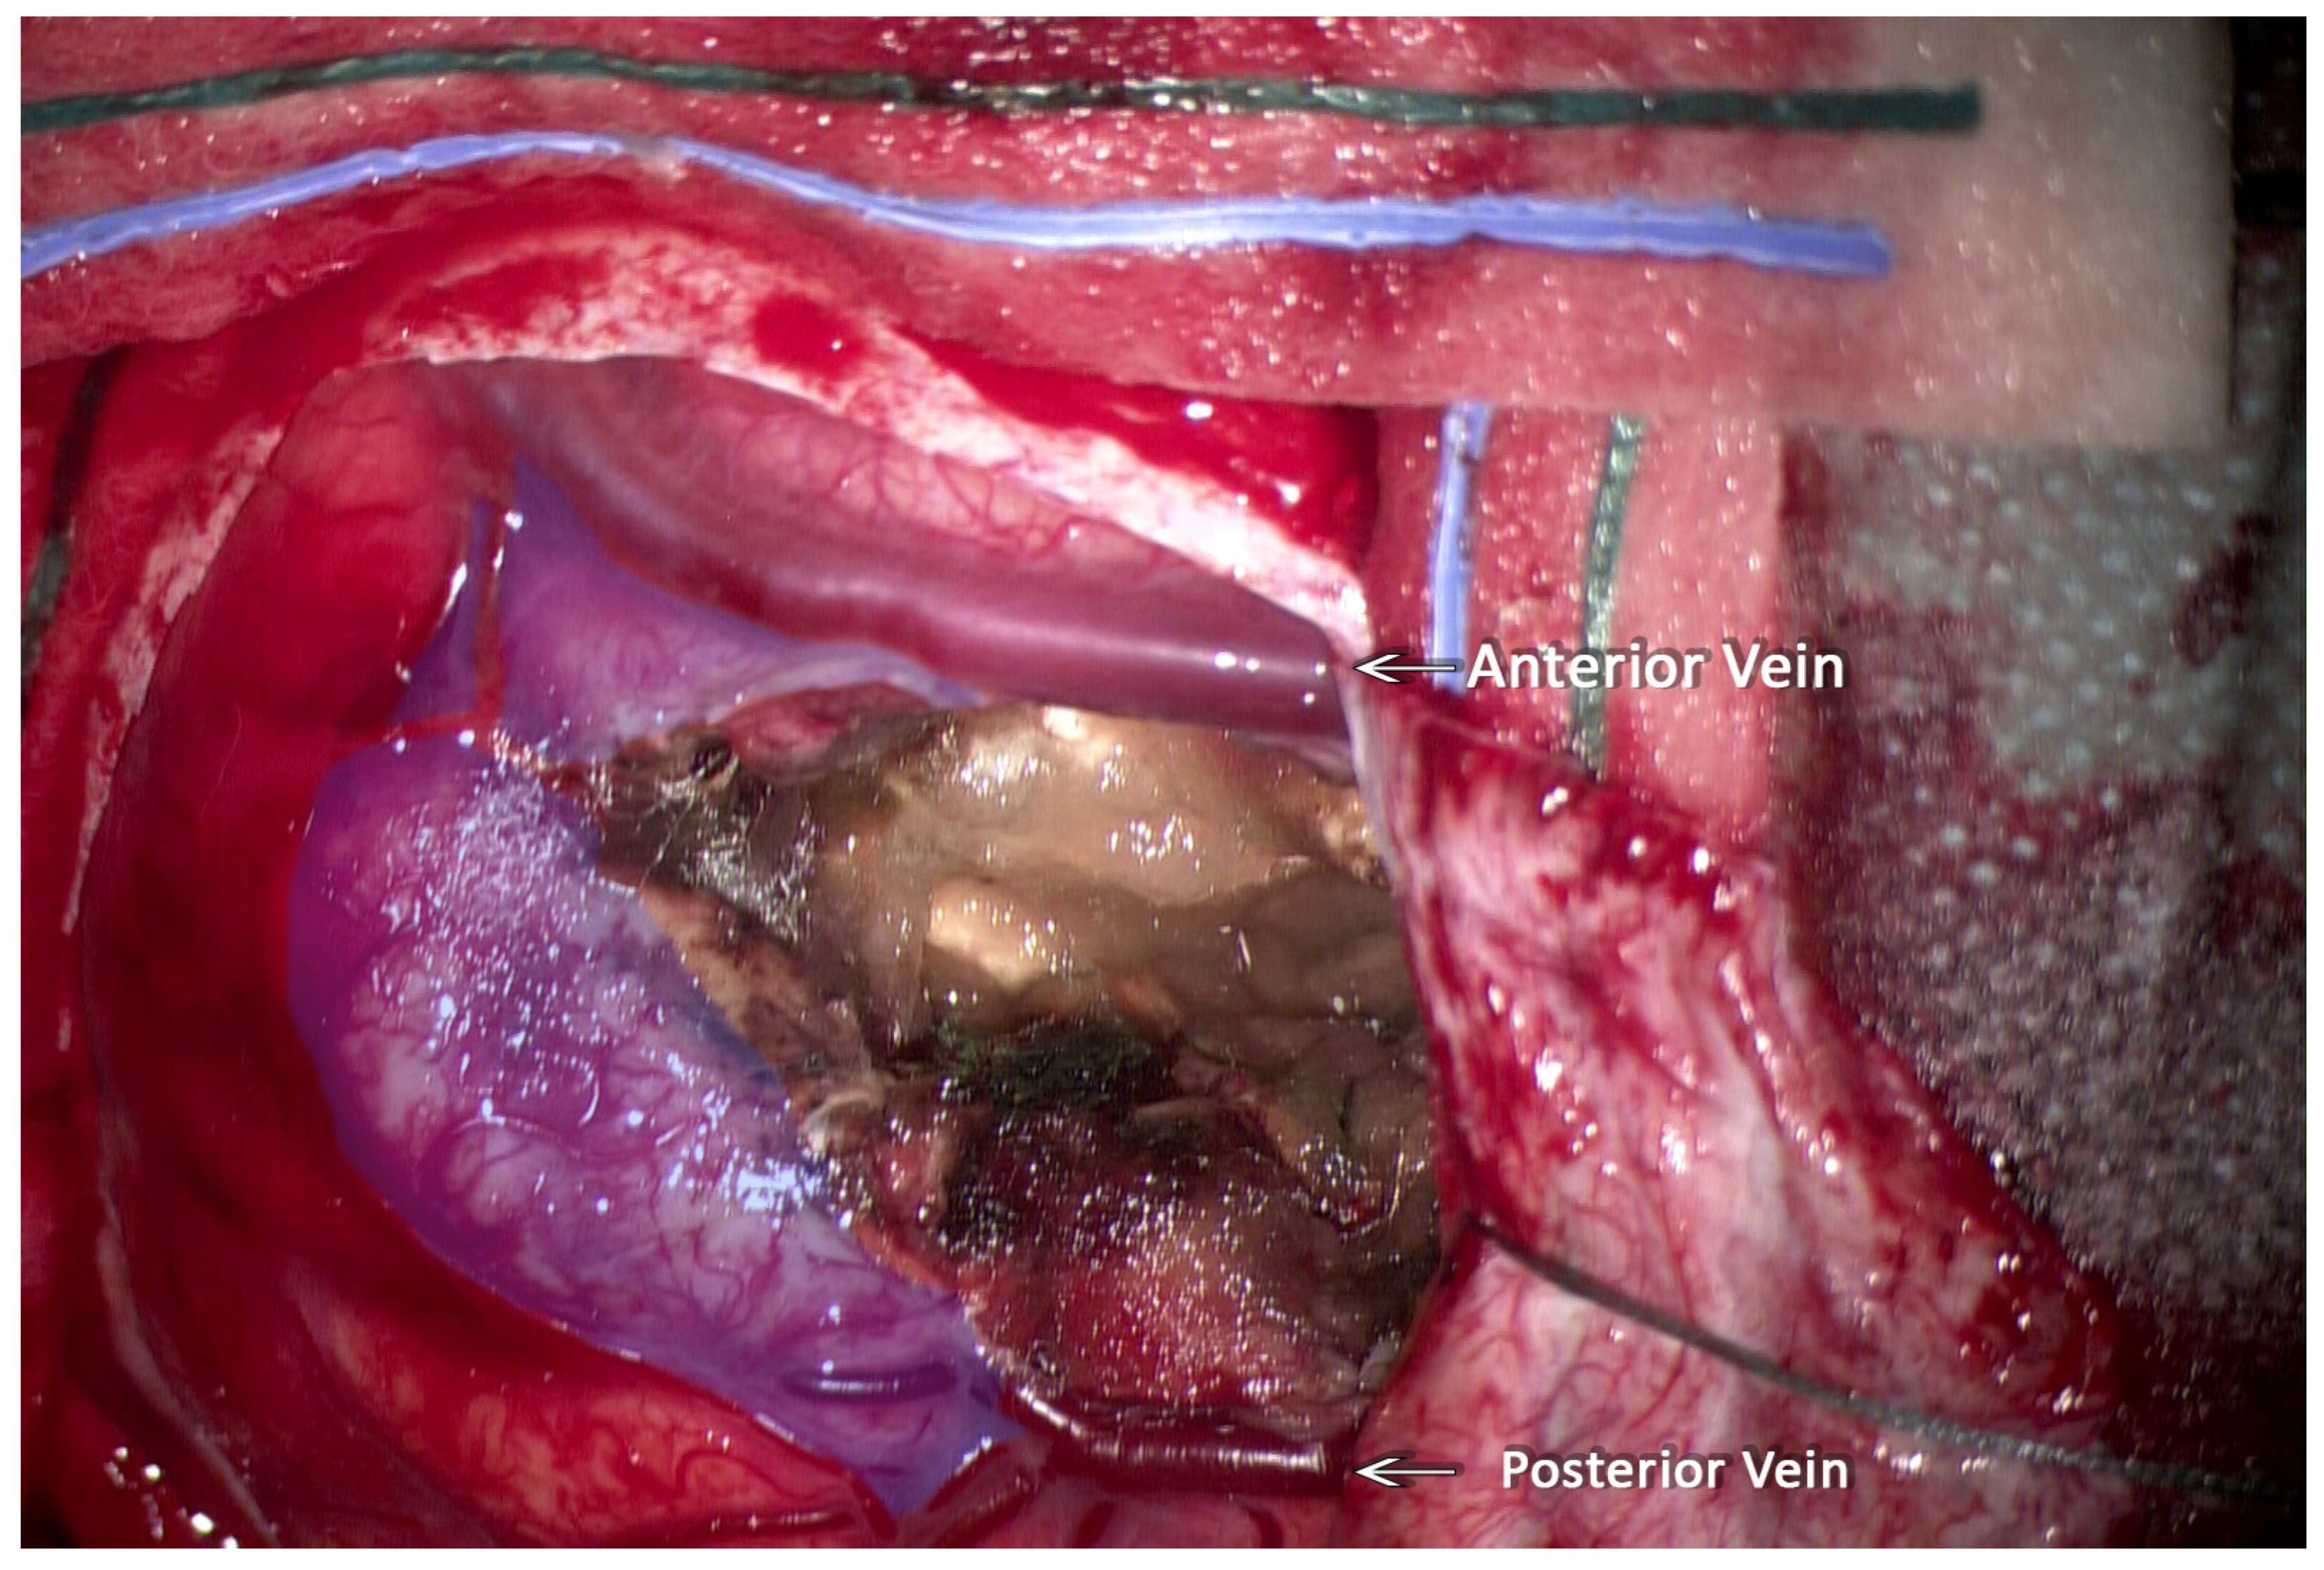

| Our case | 2023 | 8 | M | parietal | L | YES | GTR | NO |